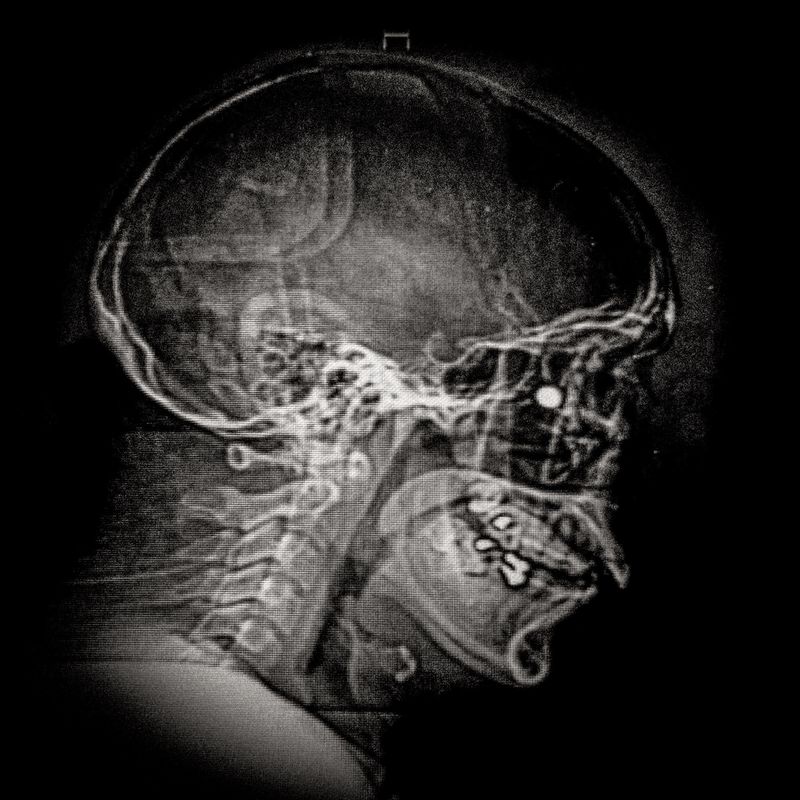

© Cristóbal Olivares - X ray showing the embedded pellet of Camilo Galvez (24) injured by chilean police during Santiago protests.

X ray showing the embedded pellet of Camilo Galvez (24) injured by chilean police during Santiago protests.

Camilo Galvez (24) Sound technician Lives in Puente Alto,Santiago Camilo was hit by a pellet that lodged into his right eye on November 15th, 2019, near the Universidad Católica de Chile in Santiago. His diagnosis was an eye burst with total loss of the right eye and fracture. “I lost an eye not because I had an accident, but because somebody shot me on purpose to mutilate me, and that is pretty hard. To think and reflect about this is very abysmal, it generates a lot of fear. When they shoot our eyes one becomes marked, it is their way of marking us, and leaves us with a psychological trauma beyond the physical mutilation.”